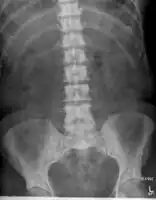

Bony metastases from prostate cancer